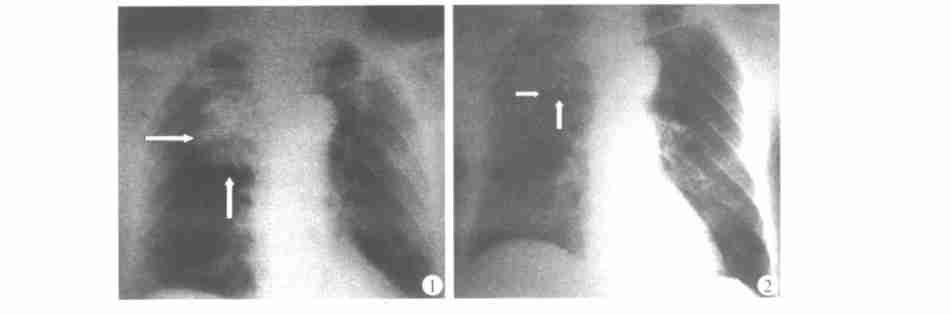

放射性粒子组织间永久植入治疗肿瘤是指通过影像学引导技术(超声、CT、MRI)经微创方式将具有放射性的核素直接植入到肿瘤靶体内或肿瘤周围,放射性核素持续释放射线。使肿瘤组织接受最大量的持续照射,从而杀死不同时段裂变的肿瘤细胞和肿瘤周围乏氧细胞,达到治疗和缓解症状的目的。而正常组织只受到极少量照射,避免了正常组织的损伤。